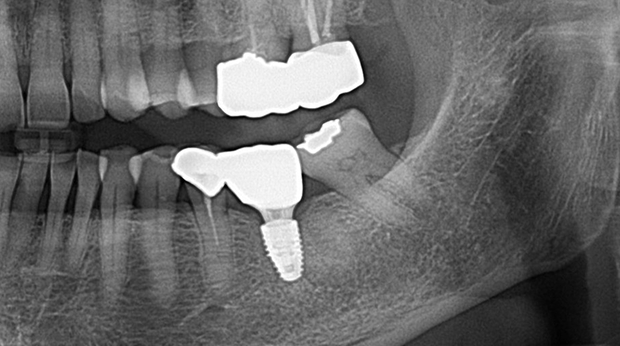

의식하진정법(수면마취)/임플란트

임플란트와 사랑니 발치는 외과적 시술로 잇몸을 절개하는 외과적 시술은

짧으면 짧을 수록 시술 후 붓기와 통증이 최소화됩니다.

치과의사 경력 14년차 구강외과 전문의가 빠르고 안전하게, 아프지 않게 수술해 드립니다.